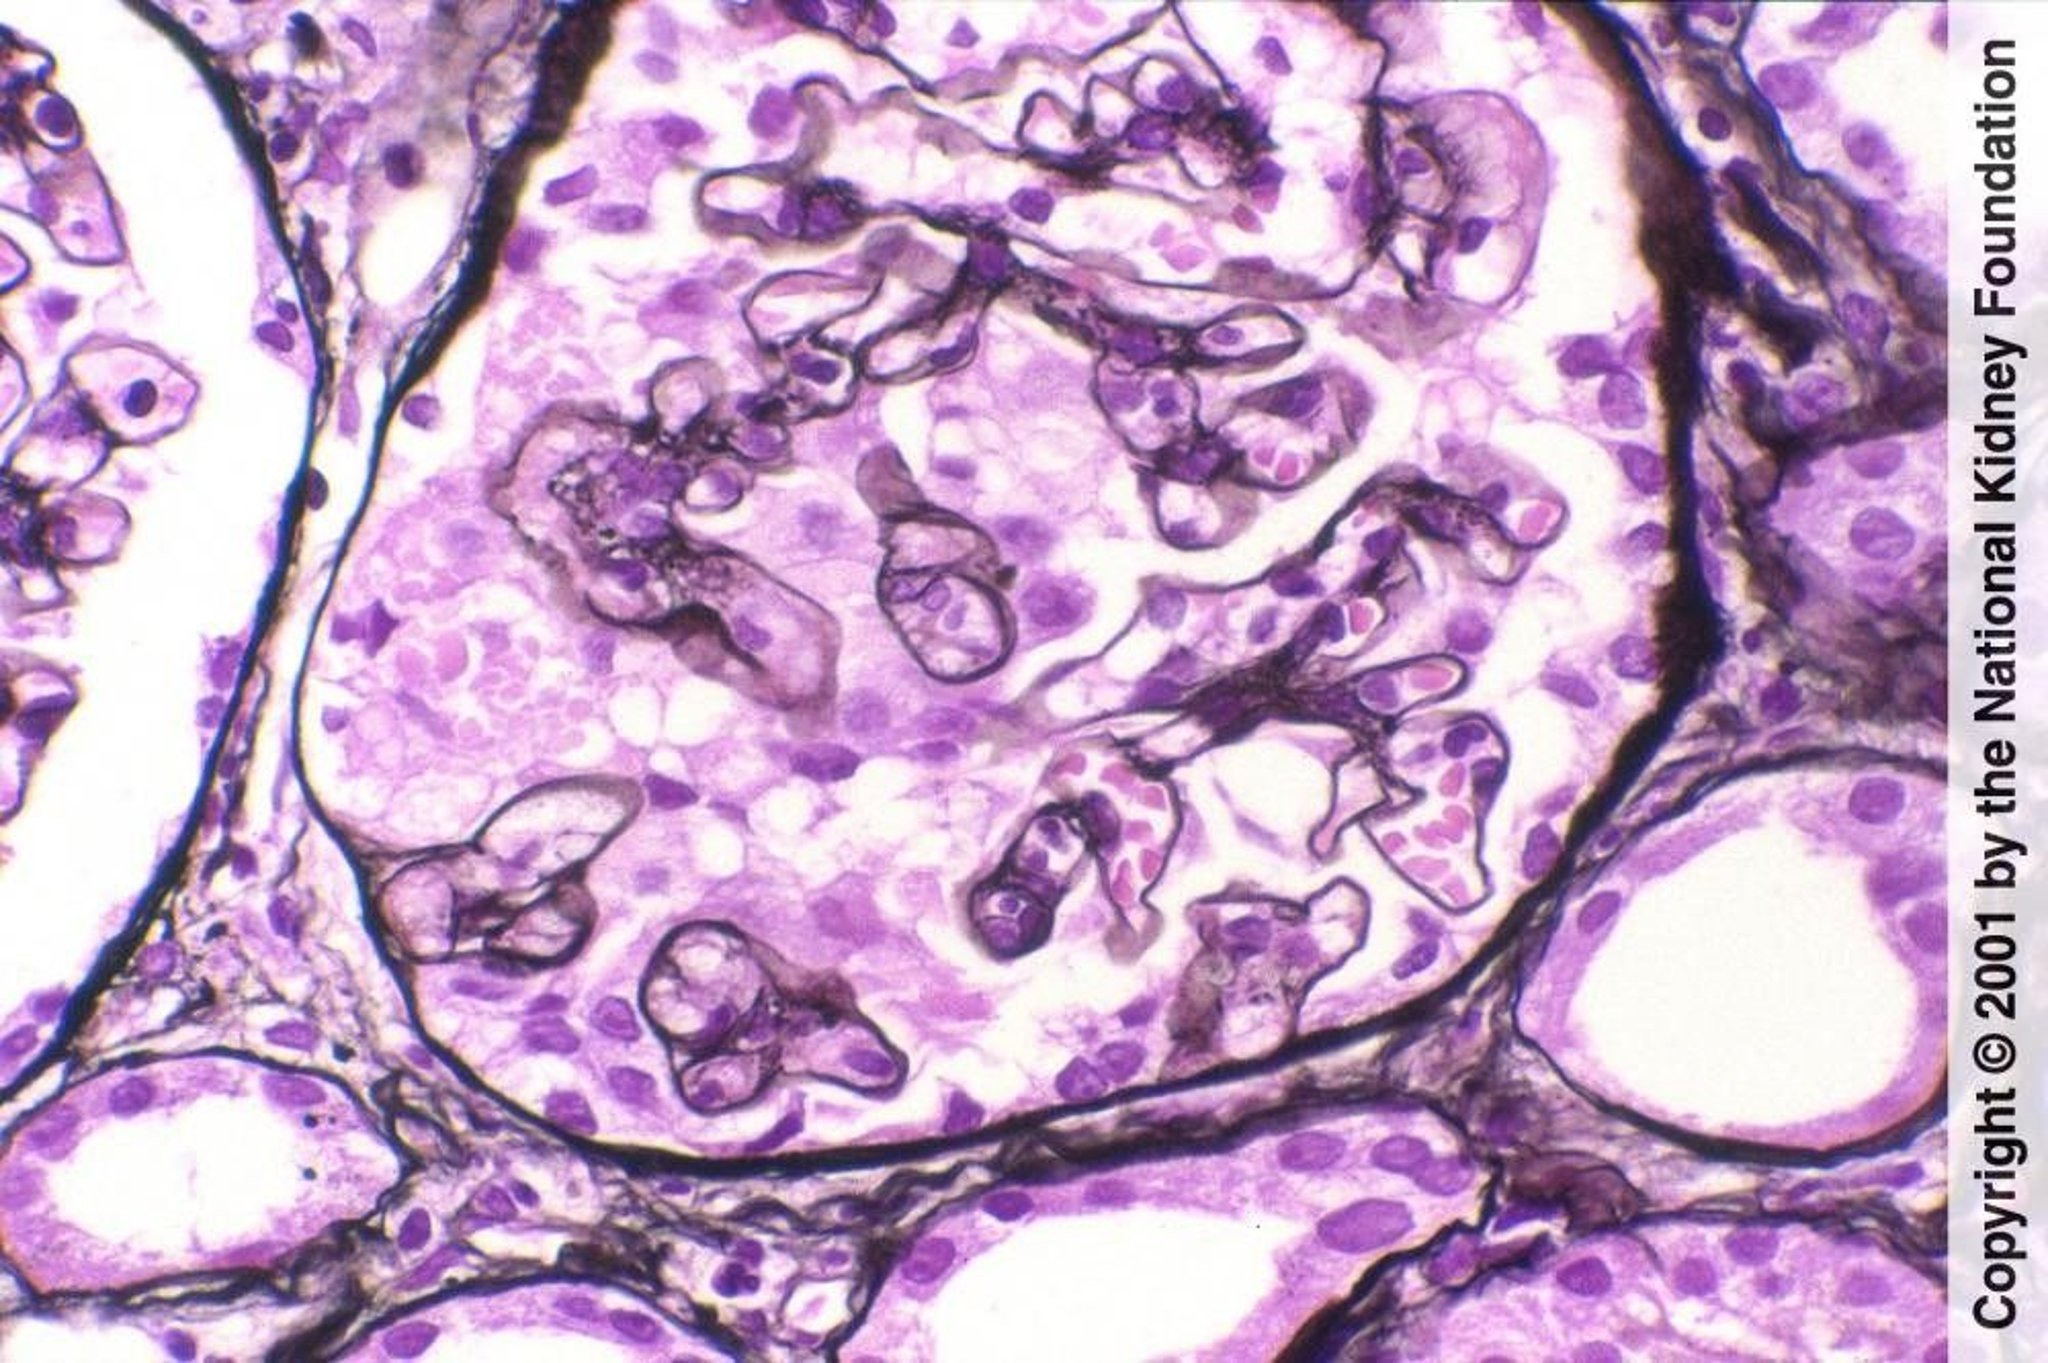

Collapsing Glomerulopathy

Wrinkling or collapse of the glomerular tuft, accompanied here by microcystic dilation of tubules, may occur with focal segmental glomerulosclerosis or HIV-associated nephropathy and is a marker of unfavorable prognosis (Jones silver stain, ×400).

Image provided by Agnes Fogo, MD, and the American Journal of Kidney Diseases' Atlas of Renal Pathology (see www.ajkd.org).